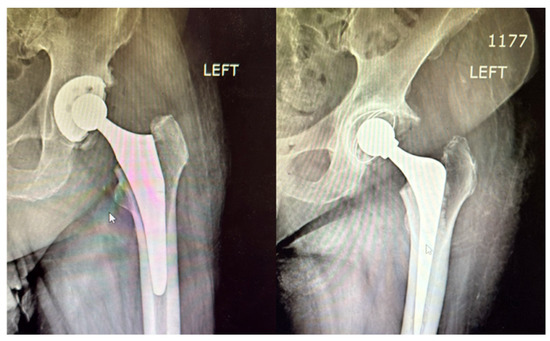

The radiographic comparison shown in Figure 15 highlights the structural differences between the two types of fixations. The cemented femoral component is surrounded by a clearly visible radiopaque cement mantle, ensuring immediate stability. In contrast, the uncemented prosthesis appears press-fit within the femoral canal, relying on its surface coating and bone ingrowth for long-term fixation.

Figure 15. Postoperative radiographic comparison between cemented (right) and uncemented (left) femoral components in THA. The cemented stem (right) is outlined by a radiopaque cement mantle, while the uncemented stem (left) shows a press-fit alignment without visible cement, relying on bone integration for long-term stability.